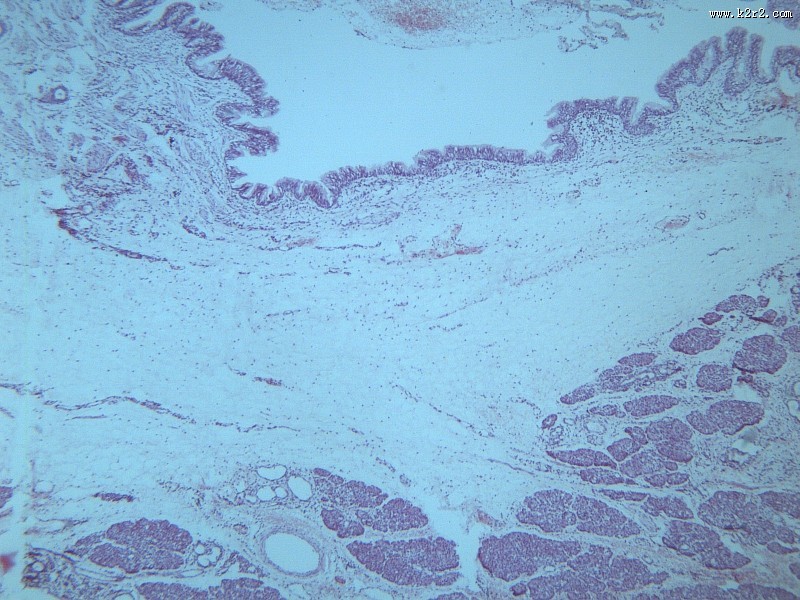

首页 > 其他类别 > 畸胎瘤(12张) > 畸胎瘤 第8张

畸胎瘤 - 第8张